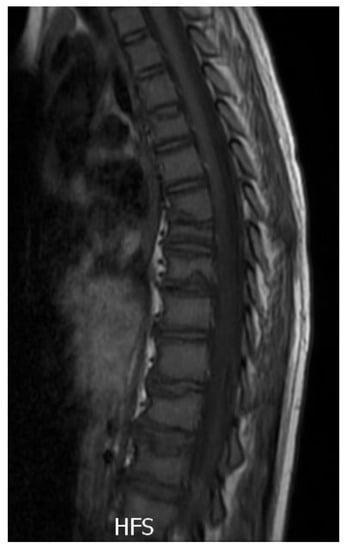

2.3. Diagnostic Assessment

2.4. Therapeutic Intervention

2.5. Follow-Up and Outcomes